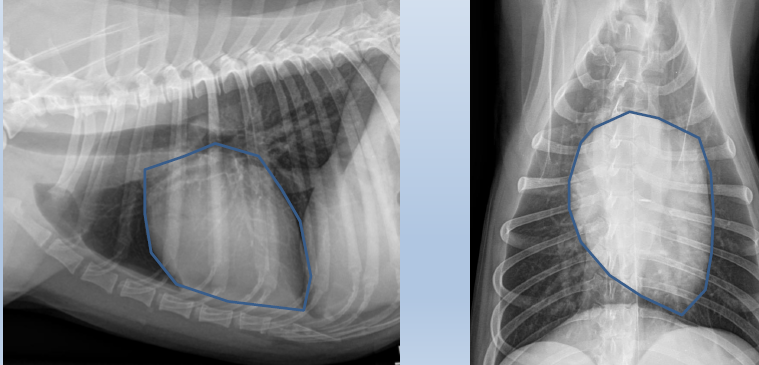

Cardiac silhouette

2 to 3

Feline

Mass on right side